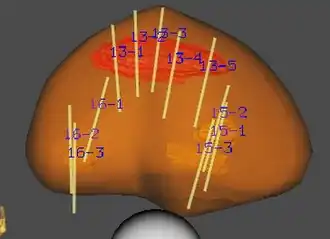

3d-reconstructed prostate gland indicating suspicious lesions for targeted biopsy |